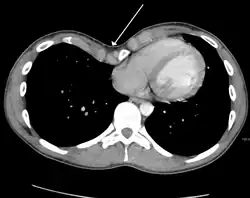

Cross sectional scan of a chest with pectus excavatum

Pectus excavatum is initially suspected from visual examination of the anterior chest. Auscultation of the chest can reveal displaced heart beat and valve prolapse. There can be a heart murmur occurring during systole caused by proximity between the sternum and the pulmonary artery.[18] Lung sounds are usually clear yet diminished due to decreased base lung capacity.[19]

Many scales have been developed to determine the degree of deformity in the chest wall. Most of these are variants on the distance between the sternum and the spine. One such index is the Backer ratio which grades severity of deformity based on the ratio between the diameter of the vertebral body nearest to xiphosternal junction and the distance between the xiphosternal junction and the nearest vertebral body.[20] More recently the Haller index has been used based on CT scan measurements. An index over 3.25 is often defined as severe.[21] The Haller index is the ratio between the horizontal distance of the inside of the ribcage and the shortest distance between the vertebrae and sternum.[22]